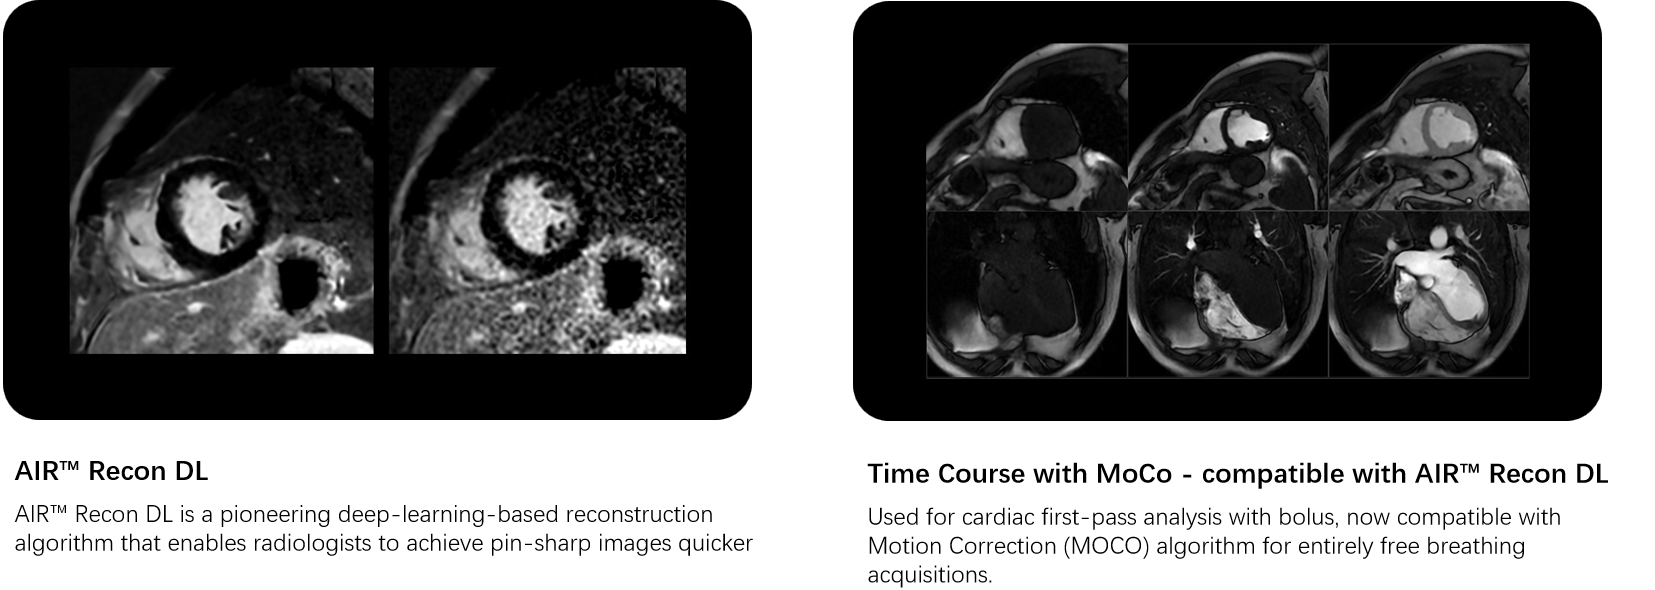

unBEATable SIGNA™ Cardiac MR Cardiac MR has been too slow, complex and inconsistent for too long1. Now with cardiac MR for SIGNA™, that’s all in the past. Experience accelerated diagnostics and crystal-clear imaging, powered by deep learning. From AI-boosted precision to lightning-fast scans, explore the seamless connection between innovation and patient-centric care..

Wide range of MR cardiovascular imaging techniques to assess morphology, flow, function and tissue viability while adapting to a wide variety of patient types.